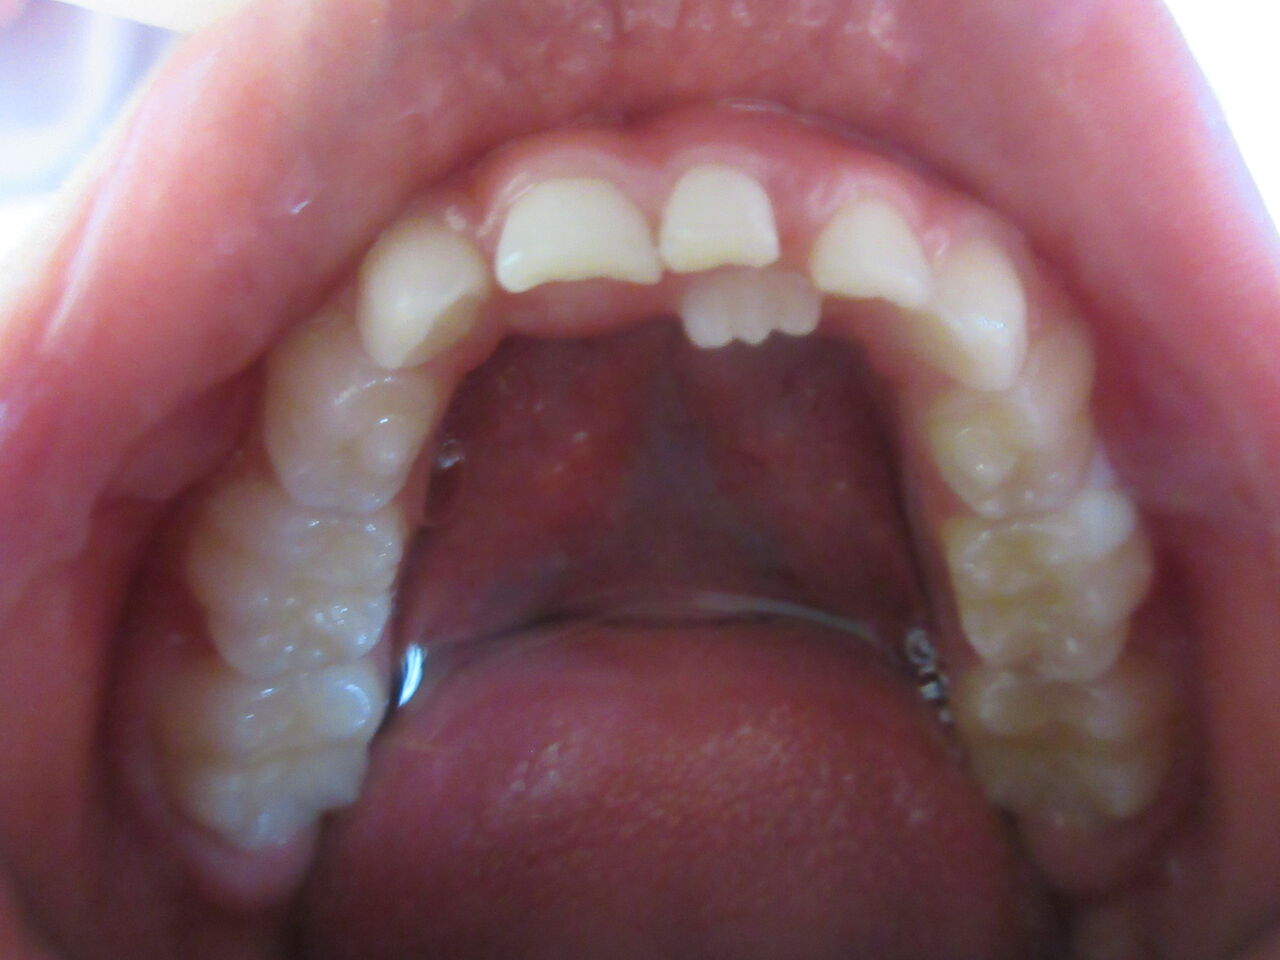

6歳ぐらいから下の前歯から大人の歯に生え変わります。このように大人の歯が内側に生えてくる場合もありますが、スペースがあれば乳歯を抜けば、自然に正常な位置に移動して来ます。